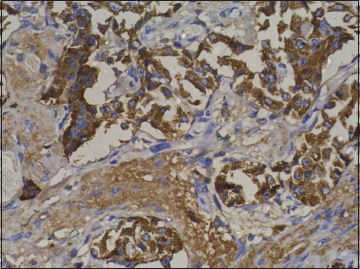

| Figure 10 Immunohistochemistry on subcarinal node showing strong positivity for chromogranin